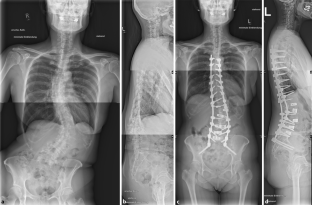

Abb. 1